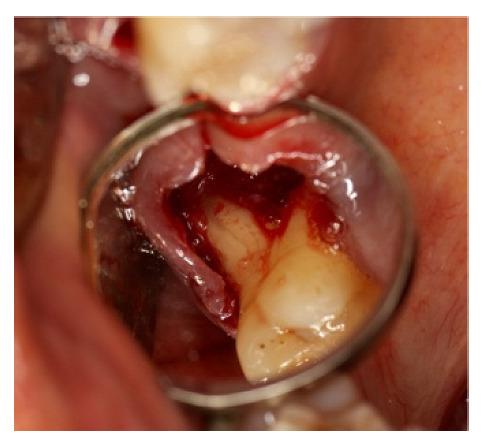

In Guided Bone Regeneration (GBR) materials and techniques are essential to achieve the expected results. Thanks to their properties, blood clots induce bone healing, maturation, differentiation and organization. The preferred material to protect the clot in Guided Bone Regeneration is the titanium foil, as it can be shaped according to the bone defect. Furthermore, its exposition in the oral cavity does not impair the procedure. We report on five clinical cases in order to explain the management of blood clots in combination with titanium foil barriers in different clinical settings. Besides being the best choice to protect the clot, the titanium foil represents an excellent barrier that is useful in GBR due to its biocompatibility, handling, and mechanical strength properties. The clot alone is the best natural scaffold to obtain the ideal bone quality and avoid the persistence of not-resorbed granules of filler materials in the newly regenerated bone. Even though clot contraction still needs to be improved, as it impacts the volume of the regenerated bone, future studies in GBR should be inspired by the clot and its fundamental properties.

在引导骨再生(GBR)中,材料和技术对于取得预期效果至关重要。由于其特性,血凝块可诱导骨愈合、成熟、分化和组织形成。在引导骨再生中,用于保护血凝块的首选材料是钛箔,因为它可以根据骨缺损进行塑形。此外,其暴露于口腔中不会影响手术过程。我们报告了5例临床病例,以解释在不同临床情况下结合钛箔屏障处理血凝块的方法。钛箔不仅是保护血凝块的最佳选择,还因其生物相容性、可操作性和机械强度特性,是引导骨再生中一种出色的屏障。单独的血凝块是获得理想骨质量并避免新再生骨中存在未吸收填充材料颗粒的最佳天然支架。尽管血凝块收缩仍需改善,因为它会影响再生骨的体积,但引导骨再生的未来研究应以血凝块及其基本特性为灵感。